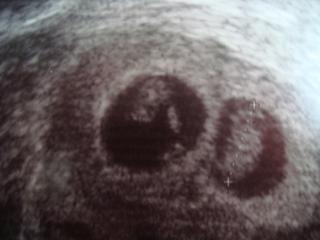

ahojky tak včera jsem byla na kontrole a rozloučit se v RF)))) bobci jsou jak májí jeden má 1.70cm a druhý 1.72cm už jsou to opravdu obříci 😀 tak snad vše půjde dobře)))

Holky nevíte, kdy je vidět srdíčko přesně? Moje kamarádka byla na ET 19.11. a dneska byla na UZ a prý srdíčko nebylo, tak vyšiluje jak blázen, ale já si myslím, že je ještě brzo, ne?